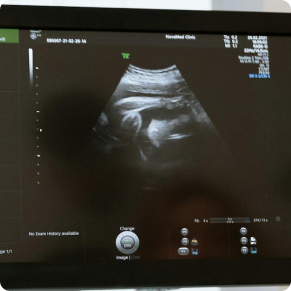

Imaging & Radiology (1)

• Ultrasound Scan-Abdomen & Pelvis